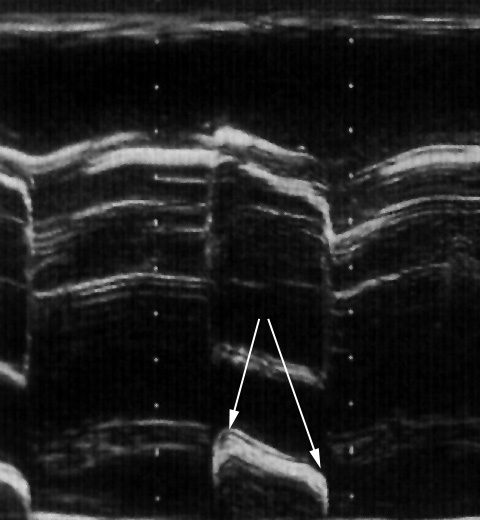

Normalerweise befindet sich im Herzbeutel nur eine minimale Flüssigkeitsmenge, die den Herzbeutel wie ein Flüssigkeitsfilm auskleidet. Diesen Flüssigkeitsfilm kann man im Echokardiogramm nicht erkennen. Bei Herzbeutelentzündungen, nach Herzinfarkten oder Herzoperationen kann man aber große Flüssigkeitsmengen im Herzbeutel erkennen (untere Abb.).

Solche großen Flüssigkeitsansammlungen im Herzbeutel nennt man „Herzbeutelerguß“. Das Echokardiogramm zeigt die Größe des Ergusses und kann dabei helfen, den Herzbeutel mit einer Nadel zu punktieren, um die Flüssigkeit abzusaugen.